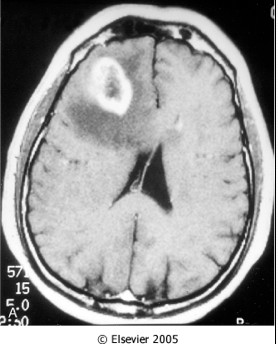

What does this image show?

The edema appears as a dark rim around the central tumor on CT.